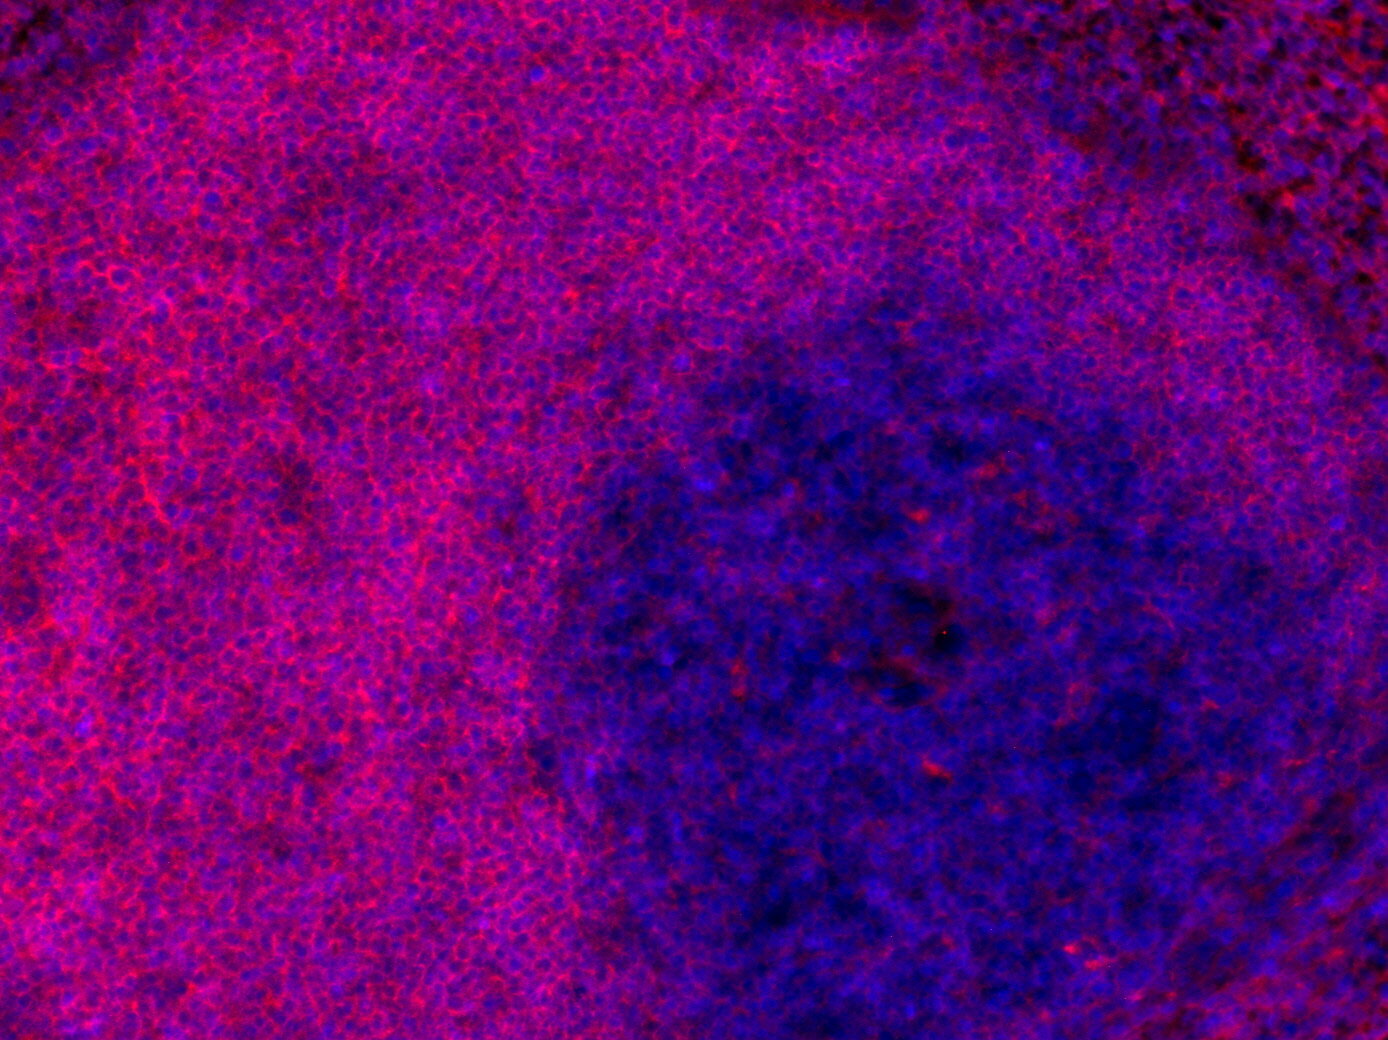

Chromogenic double staining for CD19 (DAB) and CD3e (RED) visualized T-cell and B-cell populations in the mouse spleen